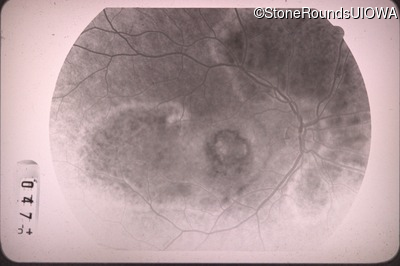

Fluorescein Angiography - Right - 20/100 -1

Exemplar